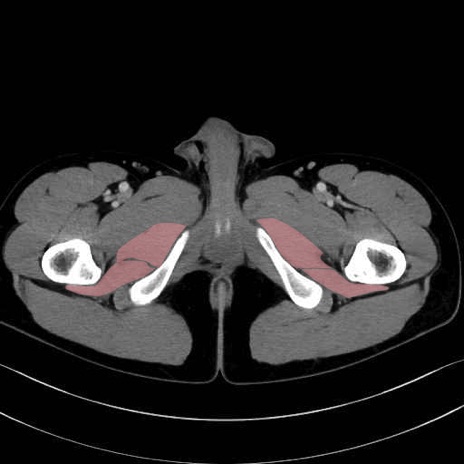

大内転筋(Adductor magnus)、小内転筋(Adductor minimus) のCT画像の解剖

6. 大腿内側(内転筋群)

大内転筋・小内転筋 (Adductor magnus / Adductor minimus)